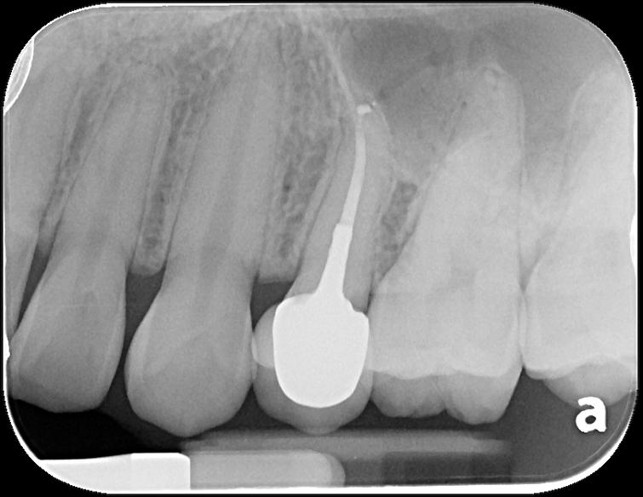

治療前,原根管治療已再污染

小臼齒顯微根管重治療